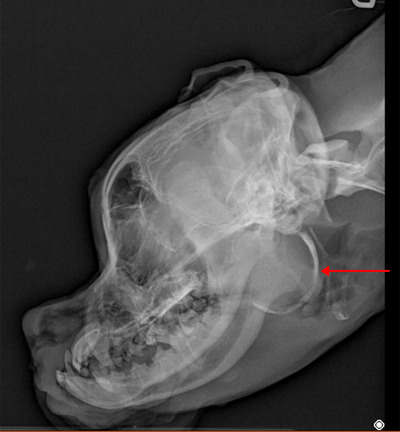

A 6-month-old, intact female Boxer presented with ongoing dyspnea, nasal congestion, cardiac arrhythmias, stertor, and syncope. A CT assessment of the head, neck, thorax, and abdomen revealed a fluid to soft tissue attenuating mass with an incomplete mineralized rim centered on the soft tissue ventral to the right tympanic bulla. Histopathologically, epithelialization was consistent with a dermoid cyst. The severe degree of mass effect caused by this abnormally and undocumented ossified structure in vital cranial cervical organs causes more systemic complications than traditional dermoid cysts. CT delineated the cyst's structure and compression/occlusion of adjacent structures.